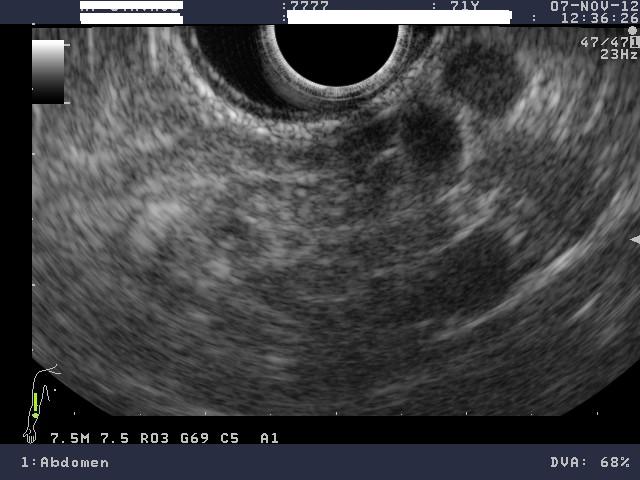

Γυναίκα 58 ετών, υποβλήθηκε προληπτικά σε υπέρηχο άνω κοιλίας όπου διαπιστώθηκε μια κύστη στην κεφαλή του παγκρέατος. Το εύρημα επιβεβαιώθηκε σε μαγνητική τομογραφία (MRI/MRCP) που δεν έδειξε άλλα παθολογικά ευρήματα στο πάγκρεας. Ο ενδοσκοπικός υπέρηχος έδειξε μια δίχωρη κύστη, διαστάσεων 6,5Χ12,5 χιλ, στην παγκρεατική κεφαλή.

Η κύστη είχε επικοινωνία με κλάδο του παγκρεατικού πόρου, ενώ ο μείζων παγκρεατικός πόρος ήταν φυσιολογικής διαμέτρου σε όλη την πορεία του. Επίσης, διαπιστώθηκε δεύτερη κύστη διαμέτρου 2,5χιλ στο σώμα του παγκρέατος που δεν είχε απεικονιστεί στην MRI.

Έγινε βιοψία με λεπτή βελόνα 22g (FNA) και αναρροφήθηκε πλήρως η κύστη της κεφαλής. Οι βιοχημικοί δείκτες του υγρού της κύστης ήταν: CEA 467, αμυλάση 1550.

Τα ευρήματα ήταν συμβατά με ένα ενδοπορικό θηλώδες βλεννώδες νεόπλασμα των κλάδων του πόρου (branch-duct IPMN).

Κύστη κεφαλής παγκρέατος

Επικοινωνία κύστης με παγκρεατικό πόρο